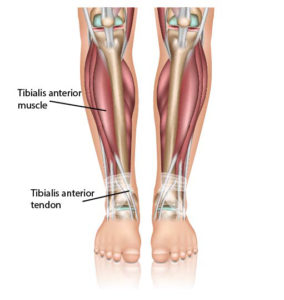

tibialis anterior

echo tibialis anterior

tibialis posterior